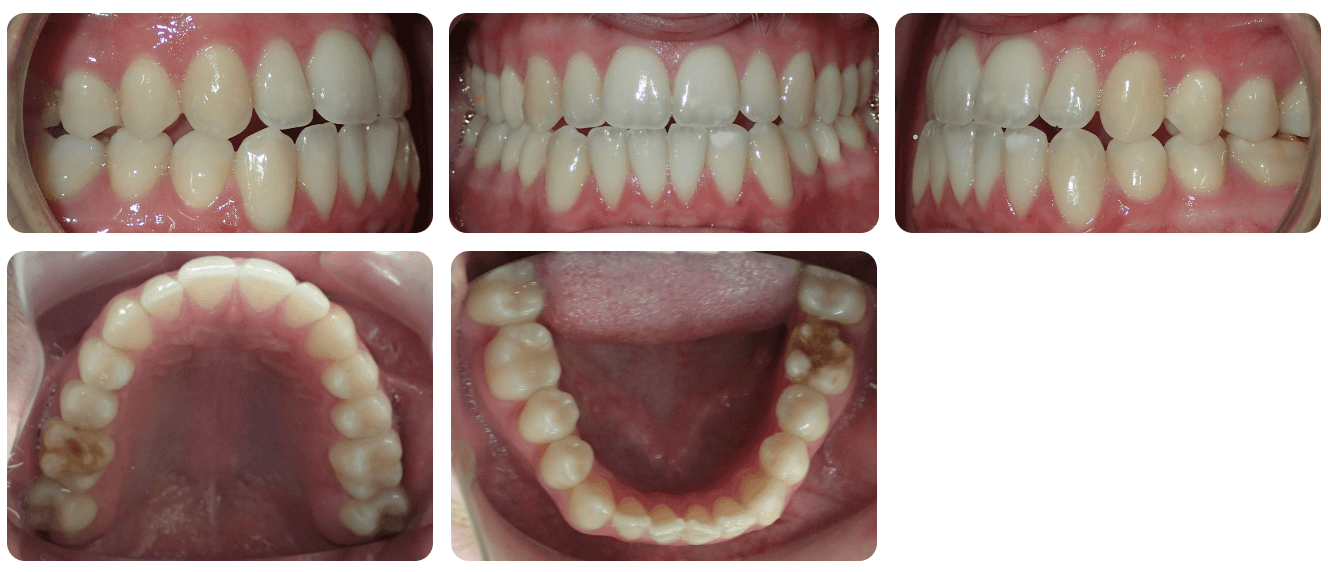

Initial treatment

INTRAORAL